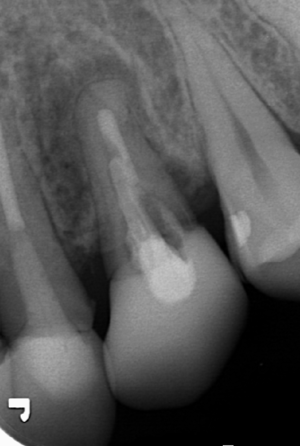

挺出終了、180度回転させて歯の安定を待つ きれいに骨が再生している

抜歯、インプラント治療を避けることが出来ました。当院では、ダメになった歯でも骨を再生することに利用できれば

すぐ歯を抜くことはせずに活用していきます。